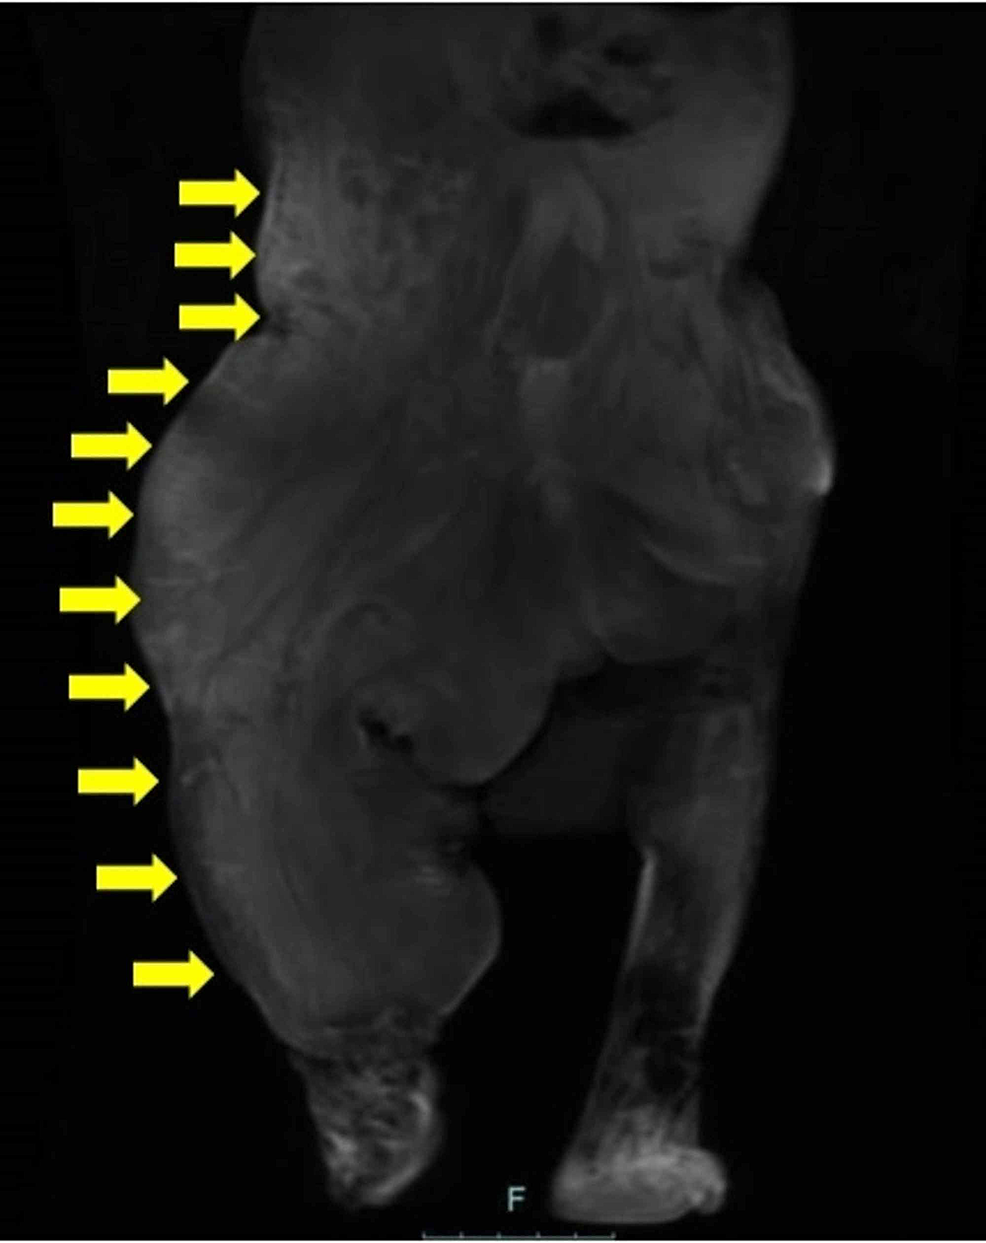

Cureus CLOVES Syndrome in a Ninemonthold Infant

CLOVES syndrome in a 5monthold boy with confirmed PIK3CA... Download Scientific Cloves Overgrowth Syndrome Cloves syndrome is a recently described rare disorder characterized by tissue overgrowth and complex vascular anomalies. Cloves syndrome is a rare disease that causes skin overgrowths in unborn children. Cloves syndrome is a rare disorder first described as a distinct syndrome in 2007. Cloves syndrome is an overgrowth syndrome with complex vascular anomalies. Learn about the pik3ca gene mutation and. Cloves Overgrowth Syndrome.

Cureus CLOVES Syndrome in a Ninemonthold Infant Cloves Overgrowth Syndrome Cloves syndrome is a rare disease that causes skin overgrowths in unborn children. Cloves syndrome is a recently described rare disorder characterized by tissue overgrowth and complex vascular anomalies. Learn about the pik3ca gene mutation and what to expect as a parent. Cloves syndrome is a rare disorder first described as a distinct syndrome in 2007. Cloves syndrome is a. Cloves Overgrowth Syndrome.